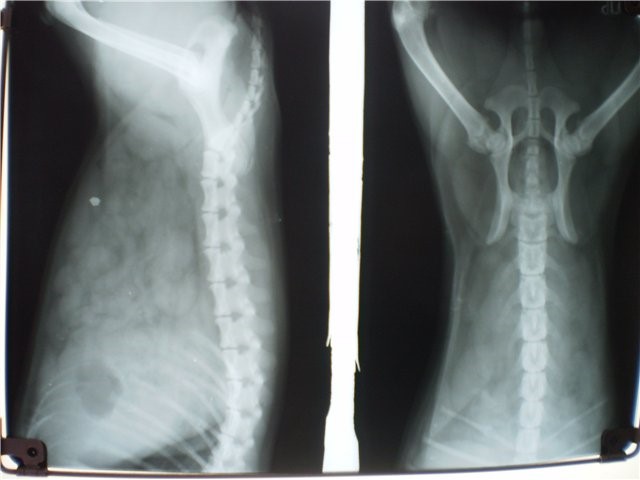

Как делают рентген? Обследование поясницы обычно проводят в двух проекциях – передней и боковой. Для этого пациента сначала укладывают на спину, а потом просят перевернуться на левый бок. В зависимости от предполагаемой патологии снимок делают либо общий, т. е. всего пояснично-крестцового отдела, либо прицельный, фиксирующий определенную часть данной части позвоночника.

Обследование поясницы обычно проводят в двух проекциях – передней и боковой

На снимке, полученном при рентгене, позвоночник представлен в виде столба, состоящего из единичных позвонков. Межпозвонковые диски, соединяющие их, заметны не так четко, т. к. хрящевая ткань более мягкая. Но даже пятна светлого оттенка позволяют увидеть различные патологии, которым подвержена данная структура.